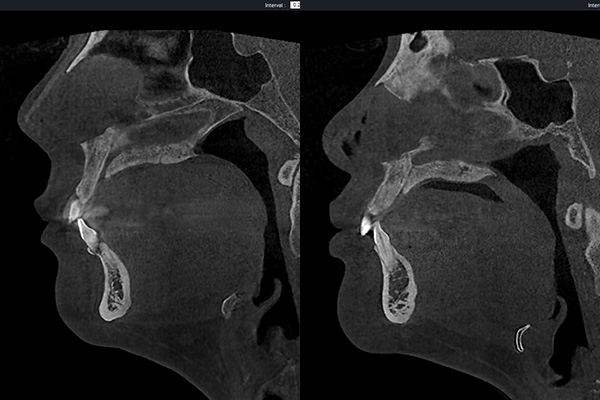

3D CT 진단 시스템은 턱 아래의 피하지방, 활경근(목근육)의 처짐 여부, 목근육 속 지방의 양, 심부볼 지방의 양을 입체적으로 확인할 수 있어, 이중턱의 원인을 정확히 구분하고 개인 맞춤 계획을 세울 수 있는 진단 방식입니다.

이상적인 턱목각도 구현

(95°~110°)설골의 위치를 확인하여 현실적인 목표를 잡고, 정면과 옆모습 모두 또렷한 라인을 완성합니다.

수술의 결과를 결정짓는 설골의 높낮이도 다르며,

피하지방과 속지방의 양, 활경근(목근육)의 두께와 처짐정도도 모두 다르죠.

정확히 진단할 수 있어야 최적의 결과를 만들 수 있습니다.